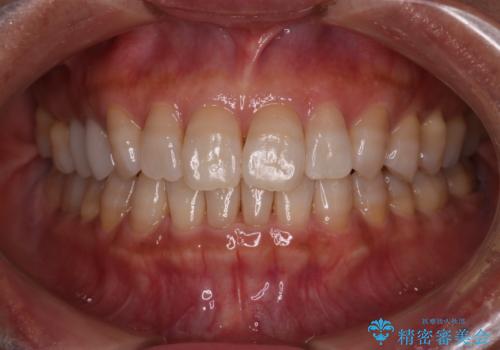

【インビザライン】下前歯だけを治したい

- 下前歯のがたつきにより唇を巻き込んでかんでしまい痛いため矯正をしたいという主訴で来院されました。今回は下顎前歯のみという強い希望があり、下顎のみのインビザライン矯正をしました。

叢生を改善するためのスペースはIPRと拡大を行いました。治療後は唇を巻き込んでしまう主訴が改善し、ご満足していただけました。